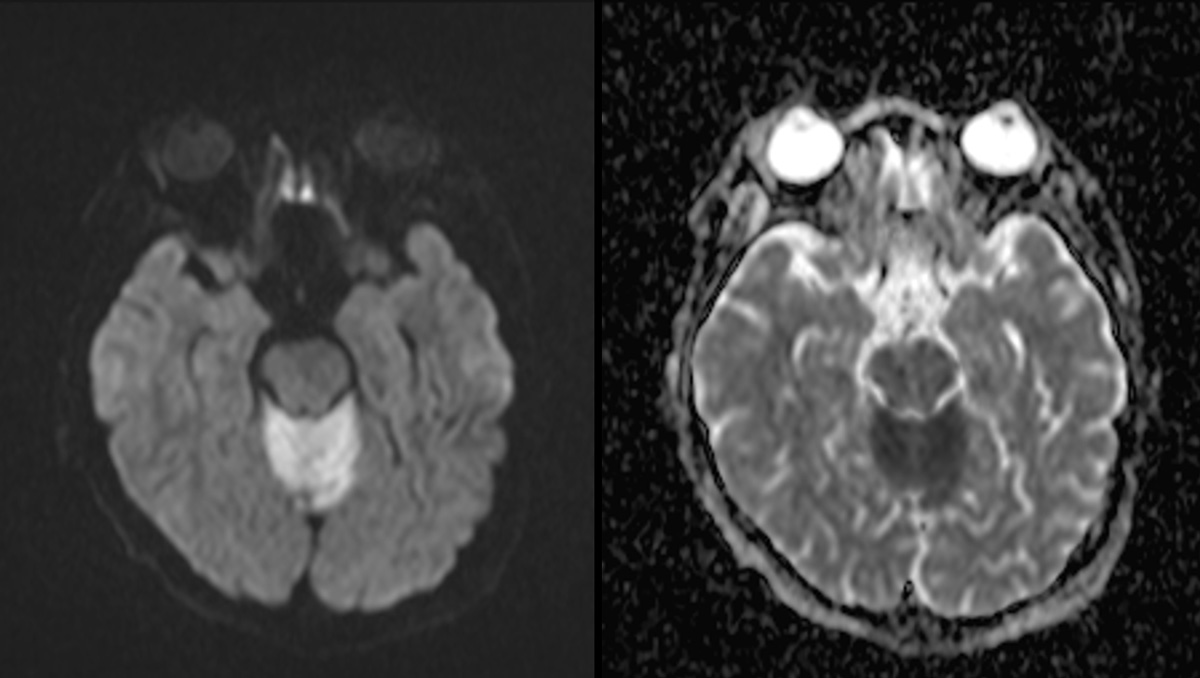

症例1:28歳男性

- 4か月ほど前から歩行時の息切れあり、1か月前から下肢の疼痛が出現、1週間前からはベッド上で生活していた。

- 3日前から呂律が緩慢となり、増悪したため、父親が救急要請。